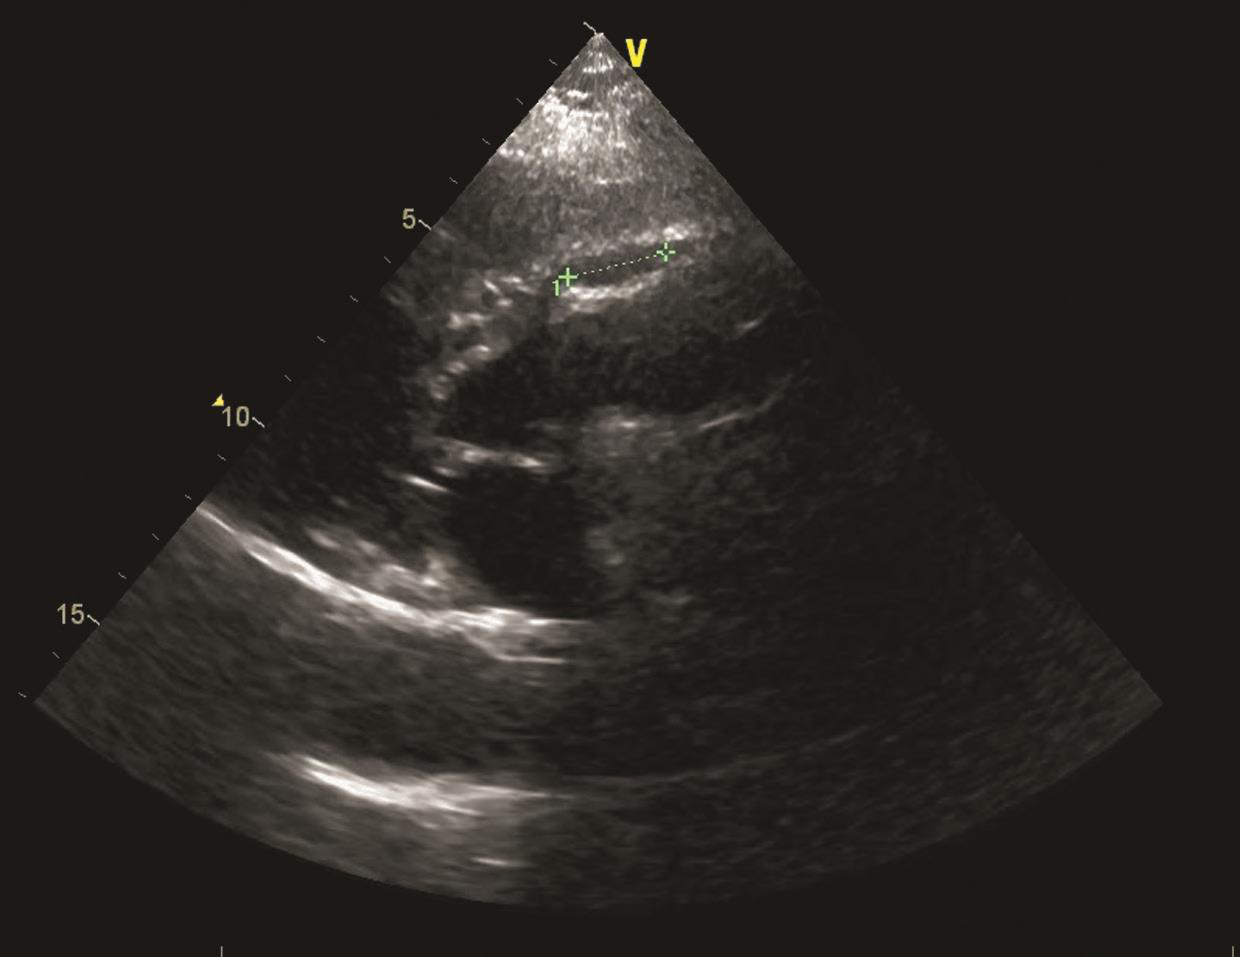

心脏超声(2011年8月29日)示主动脉扩张伴主动脉瓣反流(++++),左心房、左心室扩大伴二尖瓣反流(++~+++),右心房扩大,三尖瓣反流(++~+++);射血分数(EF)53%(图2);胸主动脉CTA示升主动脉及主动脉弓扩张(内径约5.4cm)(图3)。

图2 心脏超声(2011-08)

图3 心脏超声(2011-08)